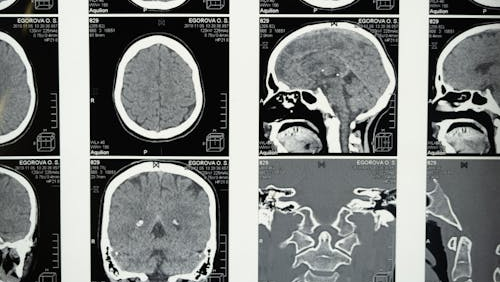

Человеческий Мозг: От Примитивного к Современному Развитие человеческого мозга представляет собой кульминацию эволюционных изменений. У Homo sapiens наблюдается значительное увеличение объема коры большого мозга, особенно в областях, связанных с речью, мышлением и самосознанием. Человеческий мозг обладает выдающимися когнитивными способностями, такими как способность к абстрактному мышлению, сложной коммуникации и созданию культурных достижений.Важной особенностью человеческого мозга является его...